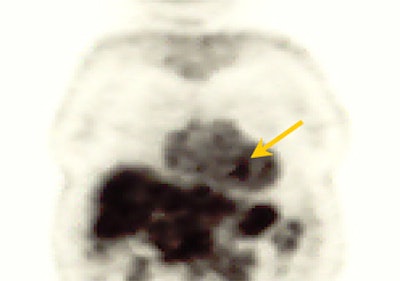

![]() |

| Study of the same patient with 25.4 mCi of Tc-99m-labeled EC-DG shows no focal areas of abnormality. Activity is noted in the stomach as well as the thyroid, indicating the presence of free pertechnetate. Images courtesy of Cell>Point. |